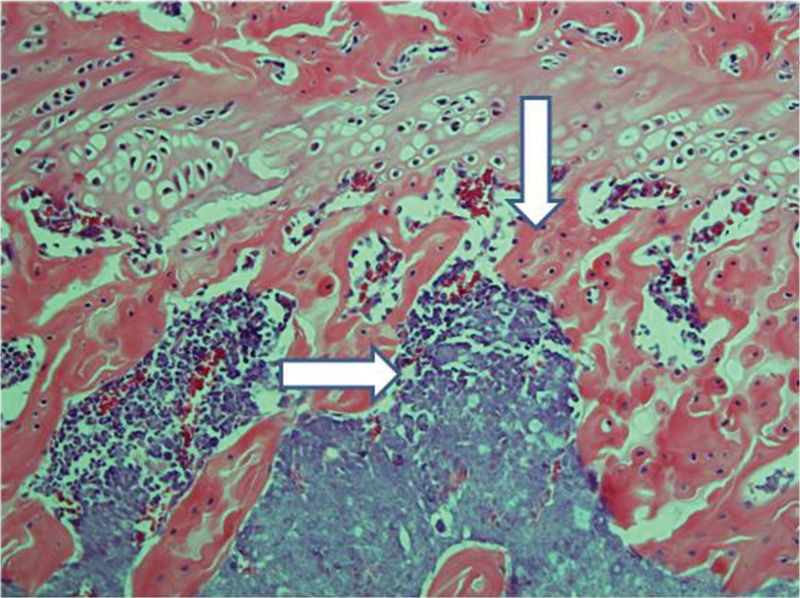

Control femurs exhibited healthy trabeculae and bone marrow histology at all times, as expected (Figure 9). On ischemic slides after 15 days, mild marrow and bone edema could be identified, along with some degree of bone marrow necrosis (Figure 10).

After 30 days, edema was no longer conspicuous. Some areas exhibited bone resorption. The bone marrow did not change substantially compared with that at 15 days (Figure 11). By 60 days, areas exhibiting extensive destruction of the bone and bone marrow could be identified. Nevertheless, as at other time points, the femur showed a generally heterogeneous pattern. Depending on the anatomical location, areas that were in fairly good histological shape were identified, whereas other areas revealed severe damage (Figure 12).

Implanted femur histology, 60 days (H&E, 100 X): Bone (upper arrow) and bone marrow (lower double arrows) degradation is more advanced. However, in keeping with the findings at 15 and 30 days, the pattern is not homogeneous, with seriously damaged areas, along with a better preserved femur.